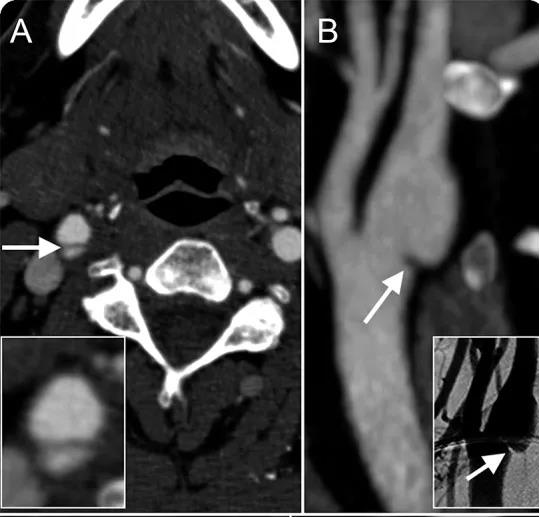

诊断要点:矢状位可见向管腔内突出的膜状充盈缺损,轴位可见隔膜样结构分隔管腔【如上图】。DSA上可见半透明的线性腔内充盈缺损;静脉期蹼远端造影剂排空延迟。